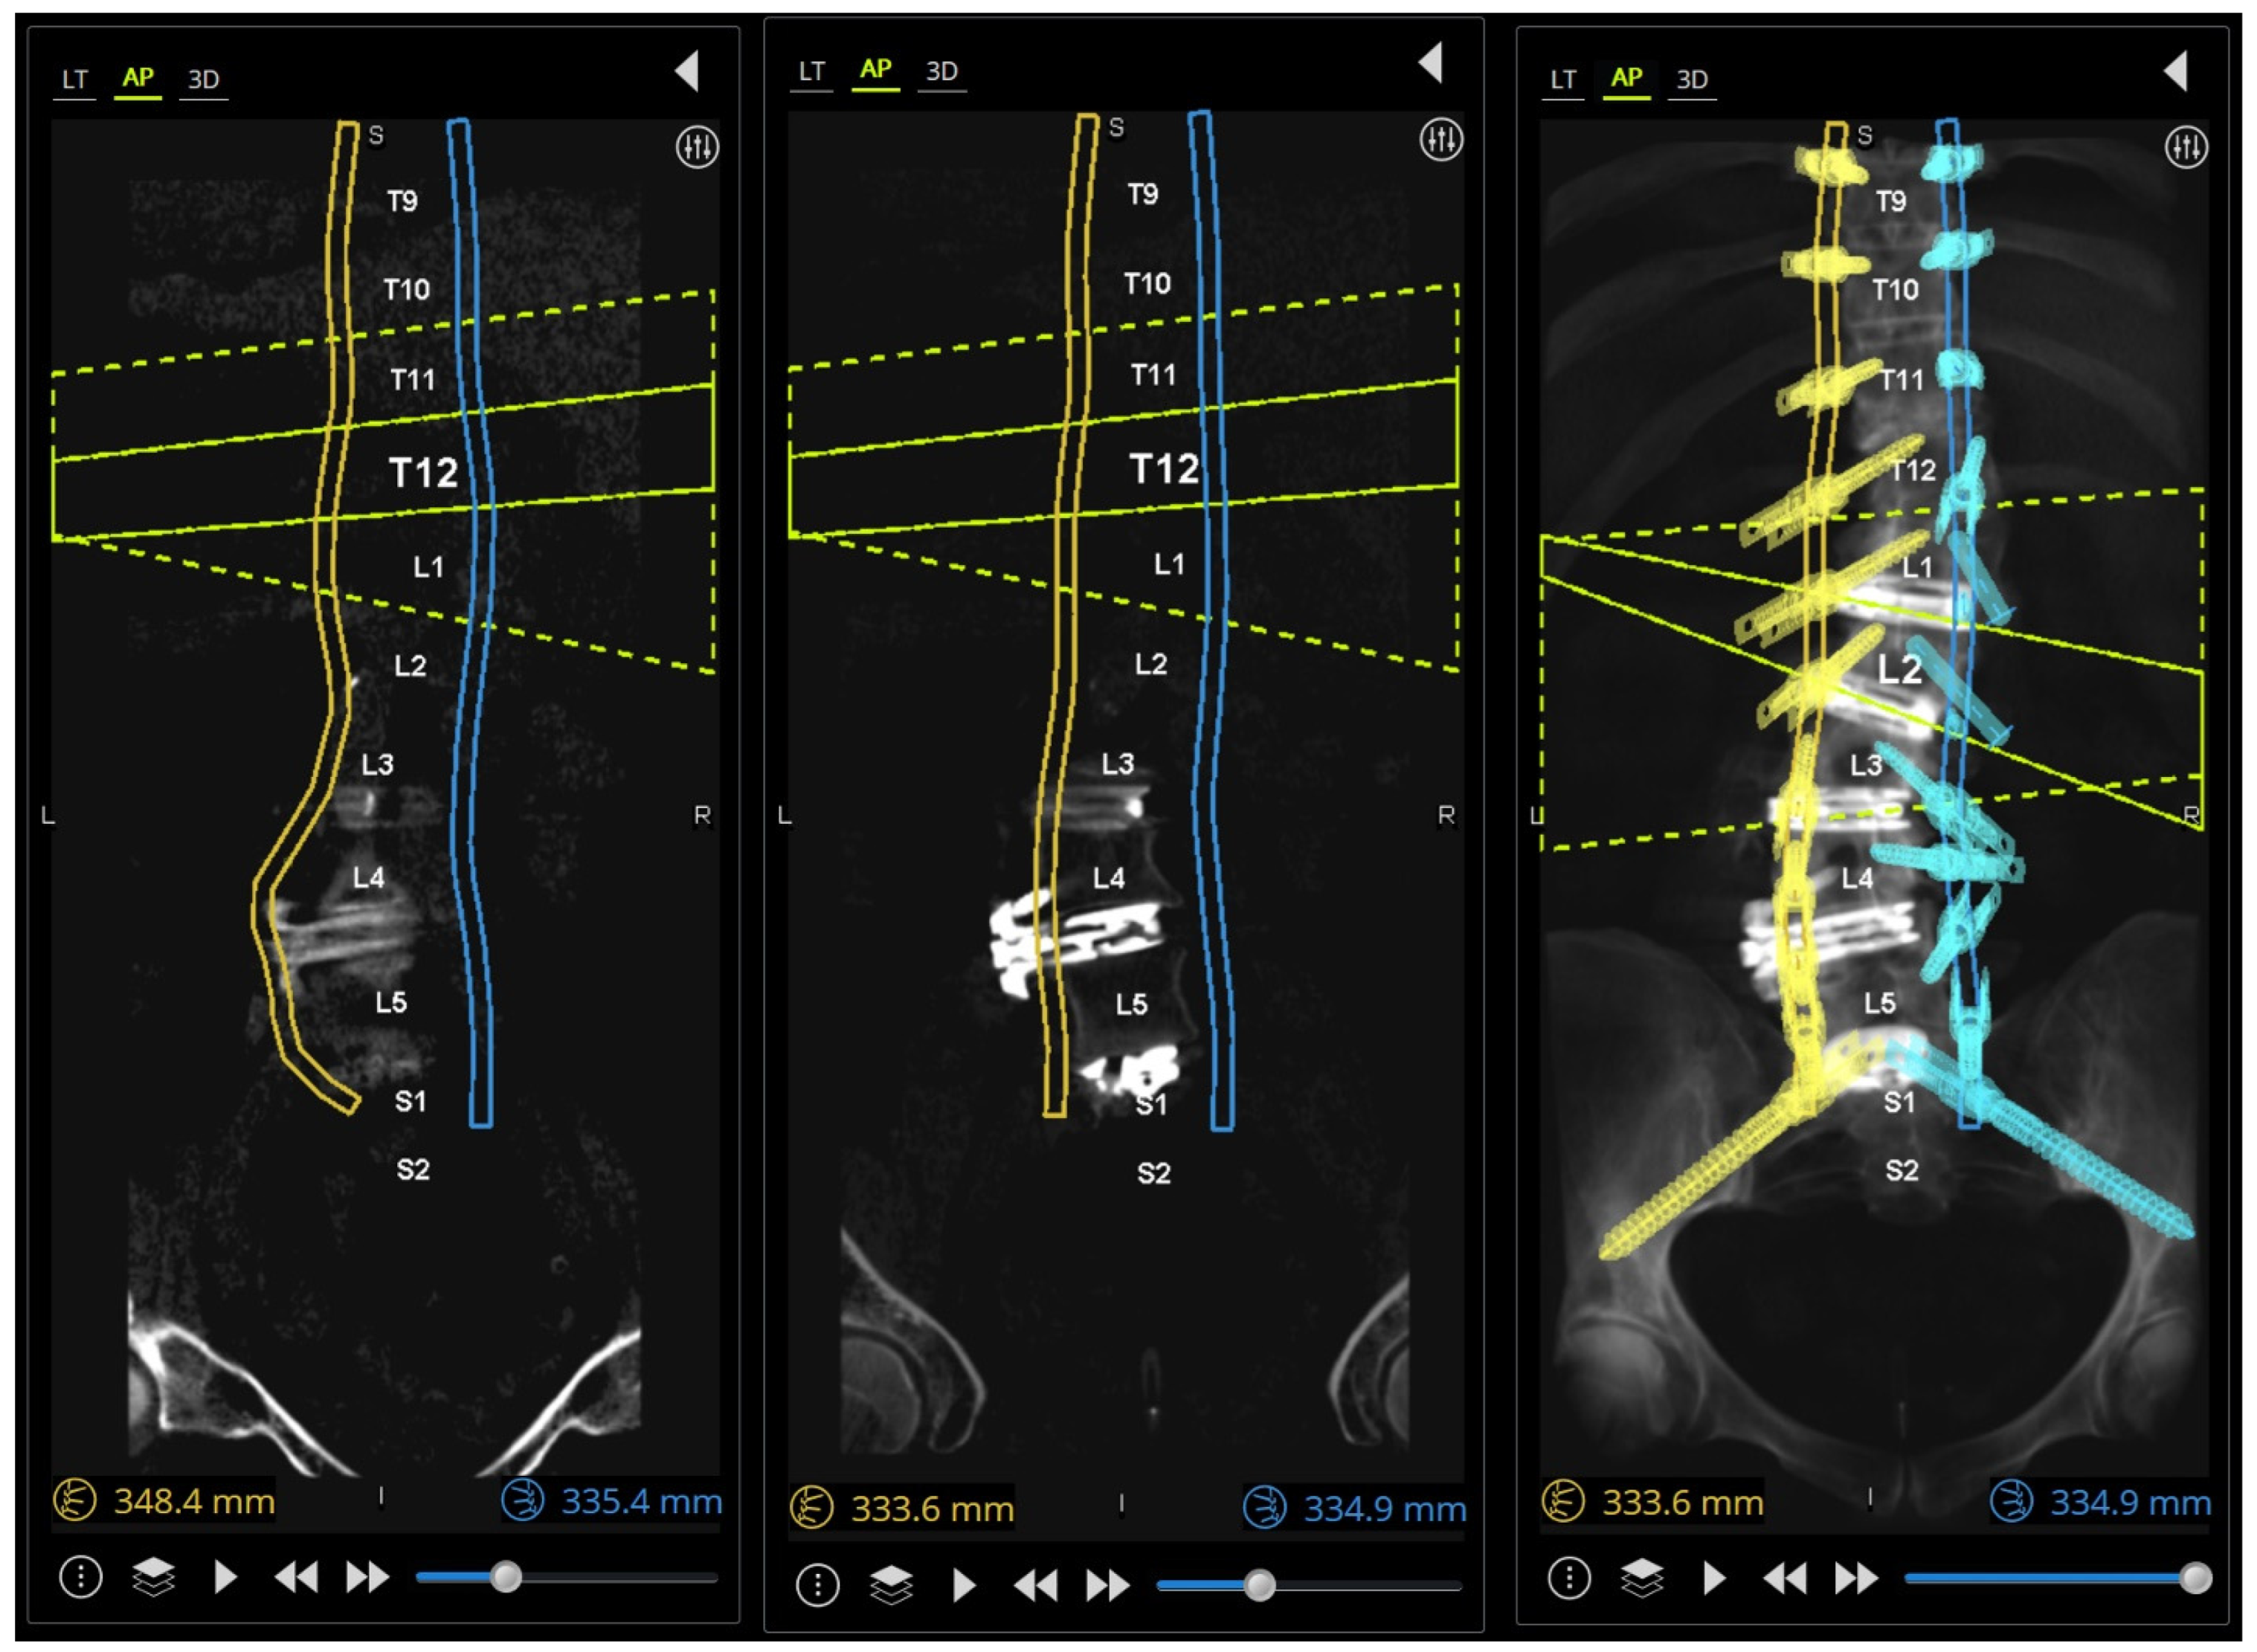

The extension towers from L4 to S2 need to be reviewed in detail because of their converging trajectories (Figure 5A), and minor adjustments can be made to the pedicle screw targeted positioning in the sagittal plane to avoid tower collisions at the skin level. If a patient-specific rod (PSR) is being used, screw planning can be performed to ensure rod geometries are appropriately similar and aligned after the simulated correction (Figure 5B).

Figure 5. (A) Three-dimensional reconstruction of the simulated rod, pedicle screws, and minimally invasive extension towers. Note the focus at the L4–S2 levels where improper planning may lead to these respective screw towers colliding and potentially blocking subsequent screw placement. Small adjustments can be made in real time in this view to resolve potential collisions. (B) (left) A patient-specific rod geometry designed with predictive parameters; (middle) the robotic plan with screws in place aligned to the simulated correction; (right) postoperative standing lateral X-ray showing good apposition to rod geometry and plan.